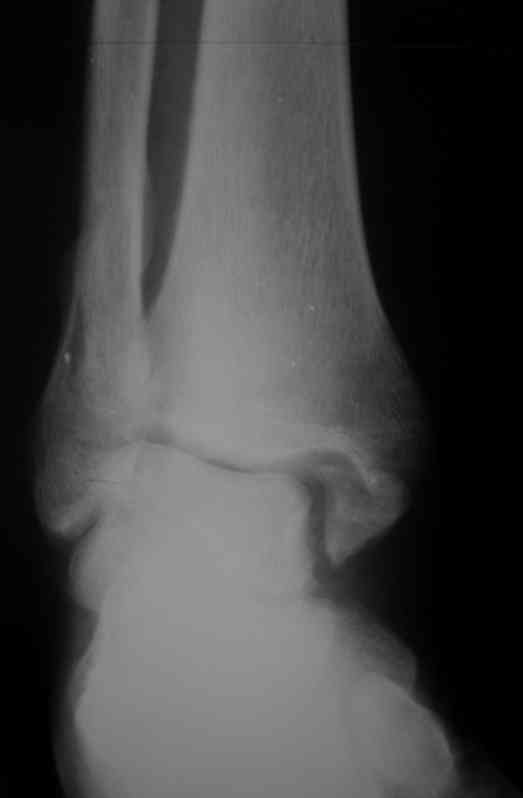

Уважаемые коллеги. Хотелось бы услышать ваше мнение по следующему случаю Обратился больной 23 года, травма 4 месяца назад - закрытый перелом наружной, внутренней лодыжки правой голени. Лечился консервативно, гипсовой иммобилизацией 8 недель, после снятия последней прошел курс восстановительного лечения. Беспокоят боли в области правого голеностопного сустава больше в проекции внутренней лодыжки, к вечеру. Отечность области сустава при физических нагрузках.Походка не изменена. Контуры правого голеностопного сустава сглажены. Имеется вальгусная установка правой пяточной кости. Объем движений в голеностопном суставе подошвенное / тыльное сгибание 50/0/80, безболезненные. Посоветуйте что делать в данной ситуации. Мне видится следующий вариант решения данной деформации: Восстановление нормальной анатомии голеностопного сустава - остеотомия малоберцовой кости и внутренней лодыжки, удалить все рубцы из области дистального межберцового синдесмоза, восстановить длину и устранить ротационное смещения наружной лодыжки.( встанет ли таранная кость на место?), фиксация наружной лодыжки пластиной, внутренней - винтами, дистального межберцового синдесмоза винтом. ЭОПом не располагаем. Что вы посоветуете? Где могут быть - технические трудности, <подводные камни>.

План вполне здравый. Но... Такое впечатление, что после устранения подвывиха суставные поверхности уже могут быть неконгруэнтны все равно.

То ли там есть импрессия в наружном отделе суставной площадки tibia, то ли не знаю что... IMHO не сильно криминальым выглядит и вариант

оставить как есть, пока не придет за артродезом.

Доступ к наружной лодыжке лучше сделать передне внутренний что бы хорошо видеть неповрежденный внутренний угол суставной вилки - это будет референс для правильной позиции таранной кости.

Доступ к малоберцовой кости тоже нужен передне - наружный для того что бы была возможность выполнить остеотомию м.берцовой и остеотомию наружной части б.берцовой. Нет сомнений, что этот угол перенес компрессию. Если не опустить эту часть суставной поверхности , то невозможно будет компенсировать валгус. Для удержания фрагмента я бы использовал 3 кортикальный трансплантат из